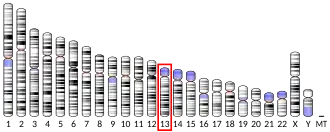

The BRCA2 gene is located on the long (q) arm of chromosome 13 at position 12.3 (13q12.3).[16] The human reference BRCA2 gene contains 27 exons, and the cDNA has 10,254 base pairs[17] coding for a protein of 3418 amino acids.[18][19]